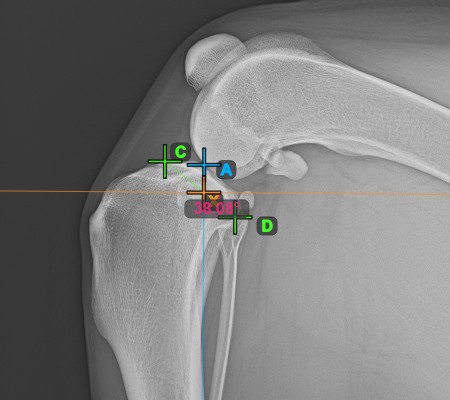

Vervollständigen Sie die TPA-Winkel-Messung, indem Sie den hintersten Punkt des Tibiakopfes (Tibiaplateau) markieren. Der TPA-Winkel wird automatisch als der Winkel zwischen der Linie, die die beiden Punkte am Tibiaplateau verbindet, und der senkrechten Linie zur Längsachse der Tibia berechnet.

Das Bild unten zeigt die übliche Platzierung des hintersten Punkts am Tibiaplateau und die automatisch berechnete TPA-Winkel-Messung.